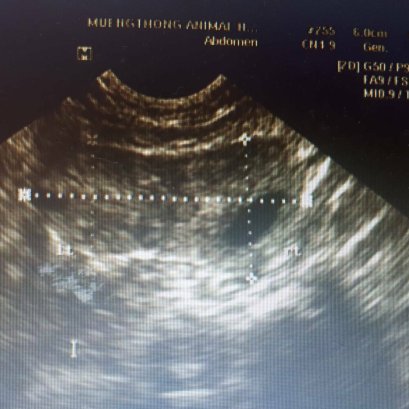

แมวผมนอนตะแคงแล้วจะเห็นก้อนปูดๆที่ท้องครับหมอ สงสัยว่าน้องจะเป็นฝี หมอคลำดูไม่มีก้อนฝีที่ผิวหนังนะคะ คลำเจอแต่ไต พบ 2 ข้างเลย มีขนาดใหญ่ เจ้าของยังสงสัยคุณหมอจึง x-ray ช่องท้องดู พบว่าไตมีขนาดใหญ่กว่าปกติ จึงต้องตรวจเลือดและ ultrasound ช่องท้องเพิ่มเติม ผลปรากฏว่า น้องเป็น ถุงน้ำในไต (Polycystic Kidney Disease)